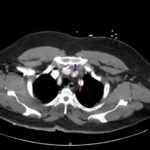

Acute aortic dissection is a life-threatening event caused by separation of the aortic layers that requires prompt management and surgical consultation. We present the case of a 53-year-old male who developed acute, severe chest pain radiating to his back at a community hospital and was transferred to a tertiary center for definitive surgical management. The patient’s aortic dissection was diagnosed via computed tomography angiography. He was started on rate-control and blood pressure medications, and was admitted emergently to the operating room. Emergency physicians should obtain immediate surgical consultation, promptly start medications for rate and blood pressure control, and administer analgesia in order to stabilize their patient and decrease the shear forces that would further propagate an aortic dissection.